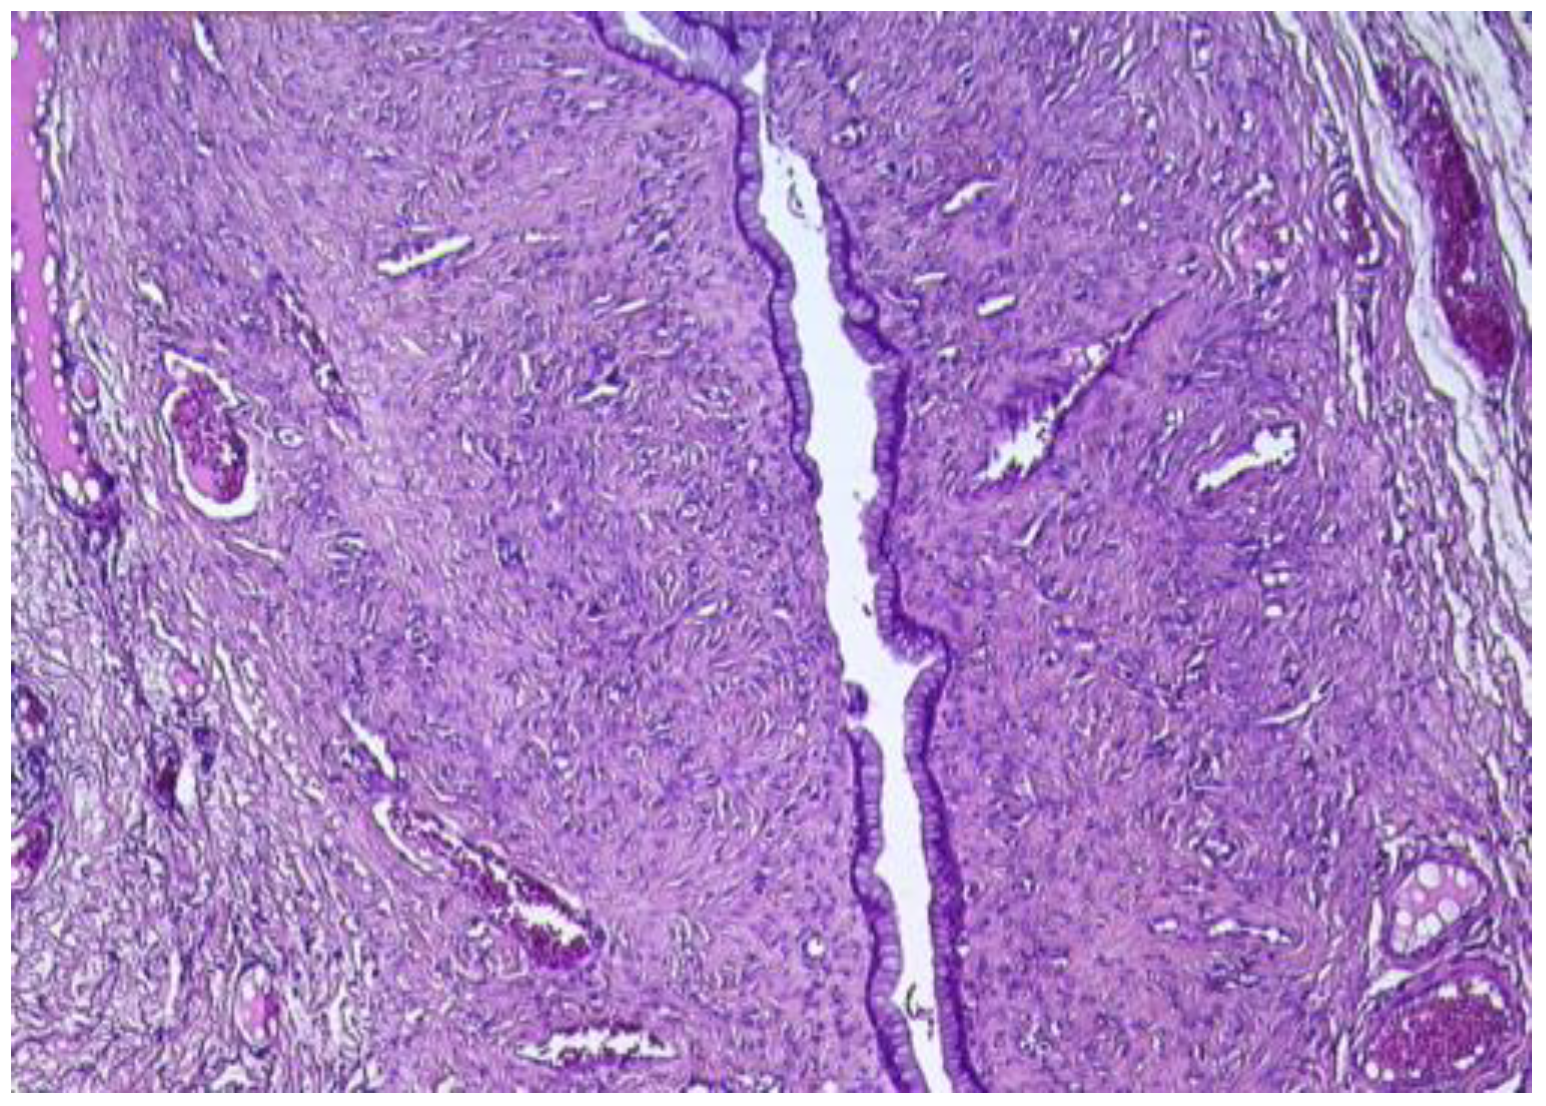

In the ovary, the microscopic exam revealed the second cyst, which was lined by a simple mucinous columnar epithelium, with focal glandular structures (Figure 7).

The epithelium presented isolated cuboidal to columnar cells with intracytoplasmic mucin and minor cytology atypia. The subjacent ovarian stroma presented luteinized areas, predominantly periglandular, accompanied by lymphoplasmacytic infiltrate, as well as rare calcifications. The remaining ovarian stroma presented follicles in different evolutive stages, atretic follicles, and a follicular cyst. Vascular ectasia was also observed.

Figure 7. Ovarian mucinous cystadenoma, lined by simple, mucinous columnar epithelium (HE ×10).